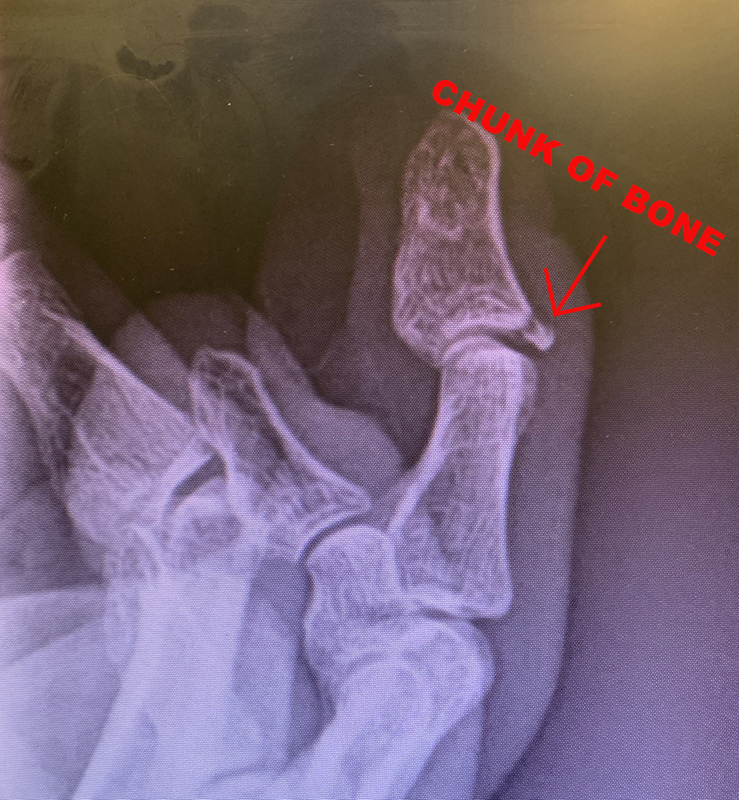

Avulsion fracture. (Which is easy to remember because it sounds like revulsion which is what happens when you think about this next part.)

Avulsion fractures happen when your tendon gets stretched WAY more than it likes but refuses to let go of your bones. Instead, the tendon pulls a piece of your bone off. Apparently my bones are no match for my tendons. Time to get back on vitamin D.

Apparently the concern with this kind of injury, besides permanently reduced mobility, is arthritis. Dr. Winter didn't say surgery, but it seems to me this is a surgery kind of situation. I'm not an x-ray technician, but that little chunk of bone seems pretty far away from the place it came from. What are the chances it (and my tendon) will reattach to the other side of the knuckle on their own?